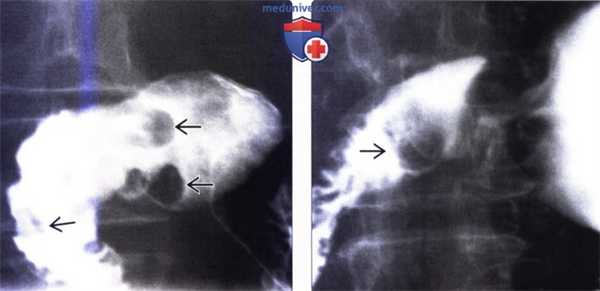

(Слева) На рентгенограмме, полученной при рентгеноскопии верхних отделов ЖКТ, визуализируются множественные мелкие подслизистые дефекты наполнения в луковице двенадцатиперстной кишки - изменения, характерные для гиперплазии бруннеровых желез.

(Справа) На рентгенограмме (кадр из рентгеноскопического исследования верхних отделов ЖКТ) визуализируется луковица двенадцатиперстной кишки, имеющая вид «клубники» вследствие наличия множественных мелких узелков в подслизистой оболочке, представляющих собой гиперпластические бруннеровы железы.